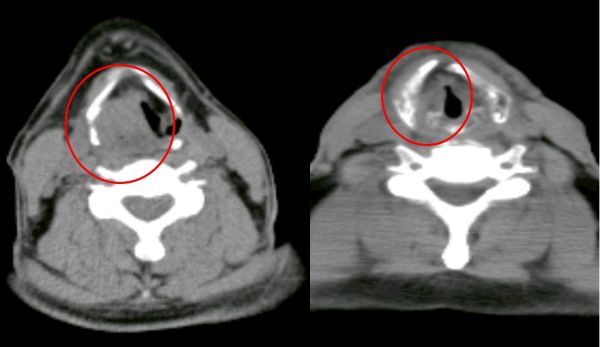

經耳鼻喉科醫師安排內視鏡檢查,於下咽部位發現可疑病灶,切片檢查後確診為下咽癌,並透過電腦斷層等影像檢查綜合評估,判定為第三期。突如其來的診斷結果,讓病人與家屬感到憂心。

經團隊評估後,該名病人先接受兩次術前免疫治療,治療期間未出現明顯不適,原本的吞嚥疼痛也有所緩解,進食與體力狀況獲得改善。隨後由頭頸外科團隊再次評估身體條件,確認達到手術安全標準,後續將安排下咽腫瘤切除手術,並依術後恢復情形持續追蹤與治療。